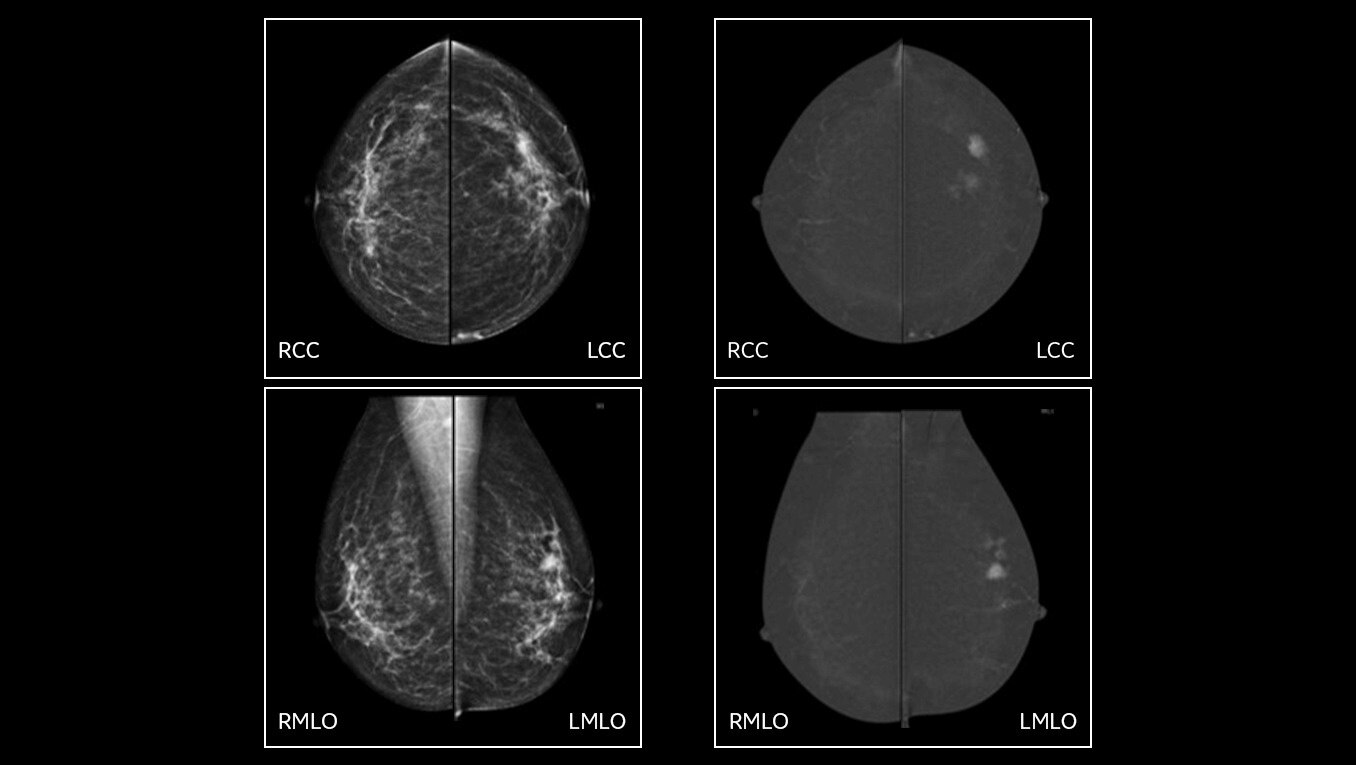

SenoBright™ HD

Contrast-Enhanced Mammography advanced application

Reduces the masking effect of breast tissue to reveal what matters1

See differently, see clearly, see in contrast

Provide answers to your patients right away and help them avoid the agonizing wait that comes with an inconclusive exam. Don’t seek, see. Accelerate your ability to make a confident diagnosis.

Astonishing clarity

The image you need is never out of reach

• Helps reduce the masking effect of fibroglandular breast tissue and increases the tumour signal1.

• Contrast agent highlights areas of unusual blood flow.

• CEM is an alternative imaging method to MRI, especially when MRI availability is limited, and for patients for whom MRI is contraindicated5.

Exceptional performance

Improve clinical accuracy

• Find lesions that cannot be seen on routine mammography6,7,8.

• Provide high specificity for low false-positives1.